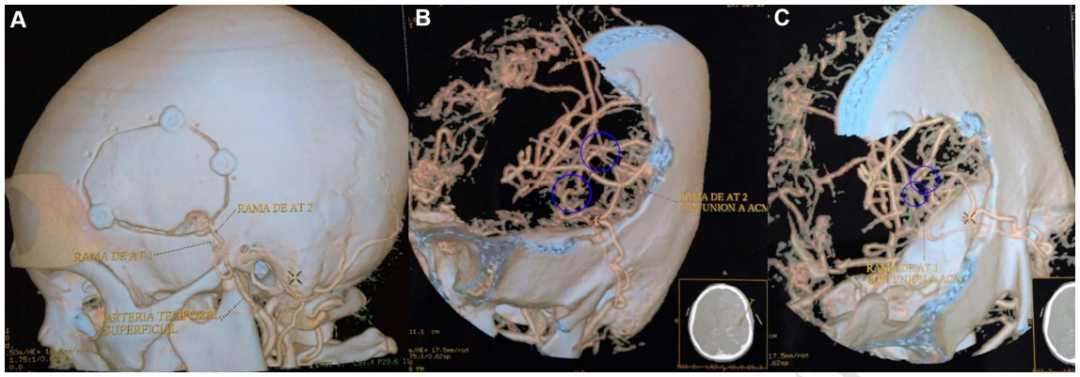

经过多方协调和国际医学合作的安排,小宇最终被转诊到日本圣路加国际医院,由世界顶尖的小儿神经血管外科专家、INC教授团成员川岛明次教授亲自主刀。川岛教授根据小宇的具体病情制定了精准的手术方案——采用直接血运重建手术,通过颞浅动脉与大脑中动脉之间的血管搭桥,建立新的血液供应通路,绕过被闭塞的血管,从而改善脑部的血液循环。

手术进行得异常顺利。令人欣喜的是,手术后的第二天,医学团队就发现小宇的语言功能明显改善——那些在术前难以表达的言语,现在可以清晰地说出来。这种立竿见影的效果充分说明了脑部血供恢复对神经功能的重要影响。术后一年的随访显示,小宇不仅头痛症状消失了,而且脑部影像学检查也验证了血管搭桥的有效性——新建立的血运通路正常地为他的脑组织供应血液,大脑血流恢复到了正常水平。小宇的智力发育轨迹也重新回到了正常的发展道路上。